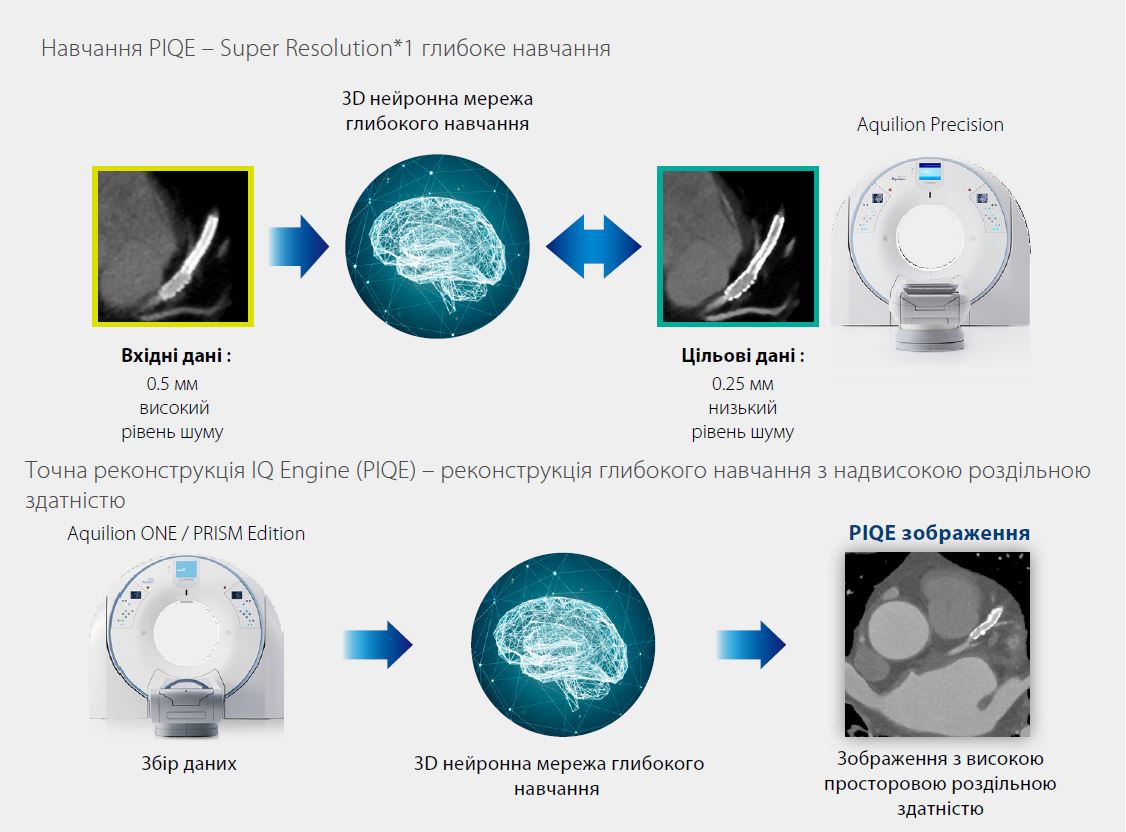

Технологія

Технологія Precise IQ Engine (PIQE) використовує потужність 0,25-міліметрових детекторів Canon Aquilion Precision для навчання3D нейронна мережа глибокого навчання. Ця тривимірна нейронна мережа наступного покоління дозволяє PIQE максимізувати притаманну просторову роздільну здатність детектора на основі об’ємного сканування ЕКГ, щоб забезпечити новий рівень якості зображення КТ серця.

Збір даних

Модель КТ: Aquilion ONE / PRISM Edition

Режим сканування: ЕКГ-синхронізація

Об'ємне сканування

Колімація: 0.5 мм

Експозиція: 120 кВ, SUREExposure

Швидкість ротації: 0.275 сек.

CTDI vol: 7.9 mGy

DLP: 103.1 mGy∙cm

Ефективна доза: 1.44 мЗв

k-фактор: 0.014*3

*1 Надроздільна здатність максимізує властиву роздільну здатність детектора.

*2 У порівнянні з AIDR 3D

*3 Звіт 96 Американської асоціації фізиків у медицині (AAPM), 2008 р.